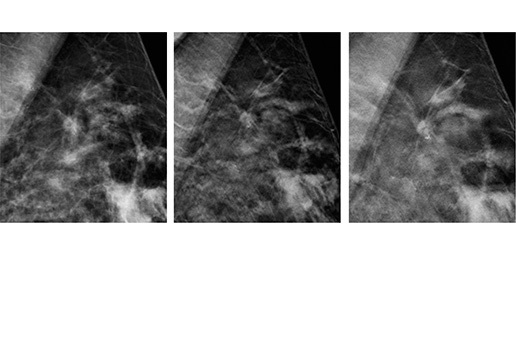

Sebastian Mroczkowski Business Development Manager, Region CEE, FUJIFILM Mammografia cyfrowa stała się standardem w badaniach przesiewowych. Pomimo kontrowersji, jakie wzbudza, jest strategią wczesnego wykrywania, która wykazała w randomizowanych badaniach klinicznych zmniejszoną śmiertelność spowodowaną rakiem sutka. Ograniczeniem tradycyjnej mammografii cyfrowej jest nakładanie się na siebie tkanek piersi, które mogą zasłonić zmiany patologiczne lub nawet spowodować, iż…